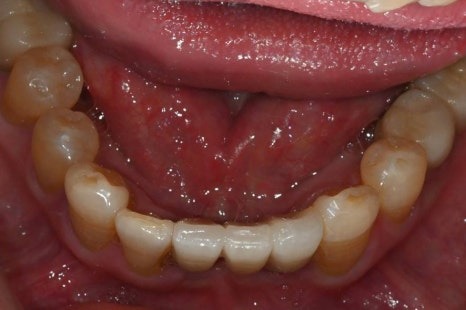

· 하악은 부분 결손과 앞니의 심한 동요

치료 계획 및 수술 과정

이 환자분은 다음과 같은 계획으로

치료를 진행했습니다.

· 수면마취(의식하 진정요법) 하에 진행

· 상악 양측 상악동 거상술 + 임플란트 10개 식립

· 하악 발치 후 결손 부위 포함 임플란트 6개 식립

임시치아부터 최종 보철까지의 과정

수술 직후에는

임시틀니 대신 고정형 임시치아를 적용하여

일상생활과 식사 불편을 최대한 줄였습니다.

· 수술 다음 날 임시치아 장착

· 하악 일부는 2개월 내 조기 보철 완성

· 상악은 뼈이식 안정화를 충분히 거쳐 진행

전신질환이 있어

치료 기간이 길어질 가능성도 고려했으나,

6개월 내 안정적으로

보철을 마무리할 수 있었습니다.

수술 후 4개월

수술 후 6개월 후 보철완료